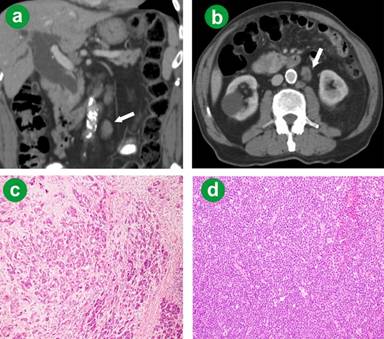

A 78-year-old man was investigated for painless jaundice and found to have a pancreatic mass. Pre-operative tumour markers were normal. LDH level was slightly elevated at 232 (reference range: 98-192 IU/L). Multiple enlarged para-aortic lymph nodes were also noted (Figure 2ab). The patient underwent an uncomplicated classic pancreaticoduodenectomy and lymph node dissection. A 3 cm pancreatic ductal adenocarcinoma was removed without evidence of lymph-node metastases (Figure 2c). The lymph nodes however contained small lymphocytic lymphoma (Figure 2d). The patient received post-operative gemcitabine based chemotherapy for pancreatic cancer. The lymphoma had not been treated at the time of last review, due to the stable nature of the disease on CT imaging and lack of symptoms. He is alive and well without obvious pancreatic cancer recurrence at 12 months follow-up.

Figure 2. a. Computed tomography identifying para-aortic lymphadenopathy, with one enlarged node clearly highlighted (arrow). b. Cross sectional images further demonstrate this finding (arrow). c. Poorly differentiated duct adenocarcinoma of the pancreas (H&E x100). d. Lymph node, small lymphocytic lymphoma (H&E x200). |